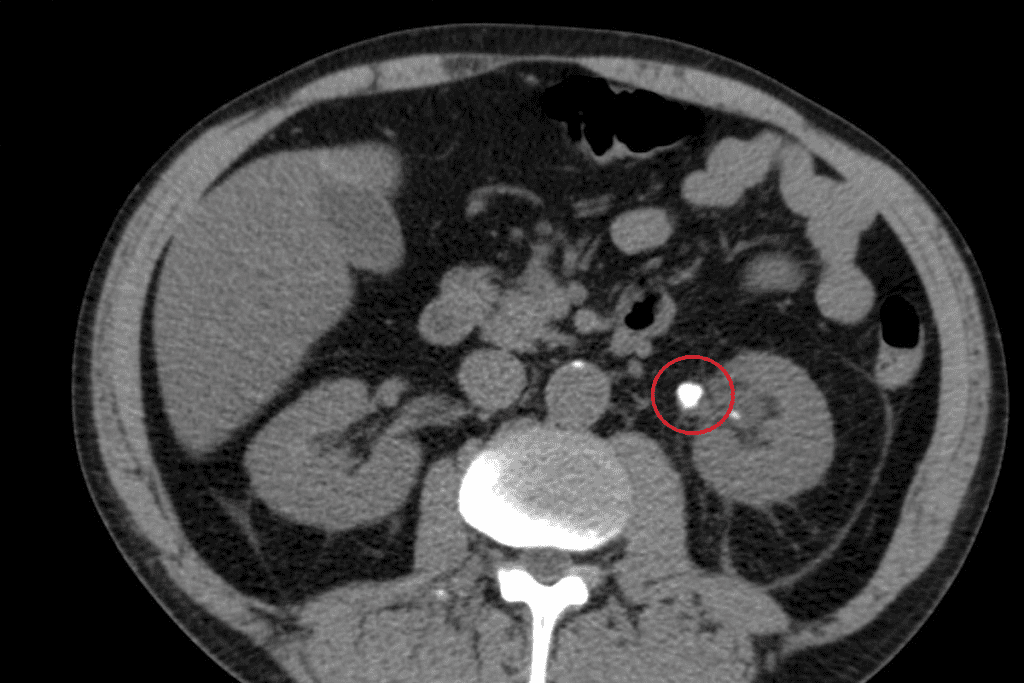

PET scans are key in medical diagnostics. They use Positron Emission Tomography (PET) to see how the body works. This is vital for diagnosing diseases in oncology, neurology, and cardiology.

PET scans use tiny amounts of radioactive tracers. These tracers go to areas with lots of activity, like growing cancer cells. The tracers emit positrons that collide with electrons, creating gamma rays. These rays are what the PET scanner detects.

PET scans detect how active the body’s cells are. A tracer, like Fluorodeoxyglucose (FDG), is used. It’s a glucose molecule with a radioactive tag. Cancer cells use more glucose, making FDG-PET scans great for finding and tracking cancer.

The PET scanner picks up gamma rays to make detailed images. These images show where the body is most active. This is super helpful for diagnosing and keeping an eye on diseases like cancer, brain disorders, and heart issues.